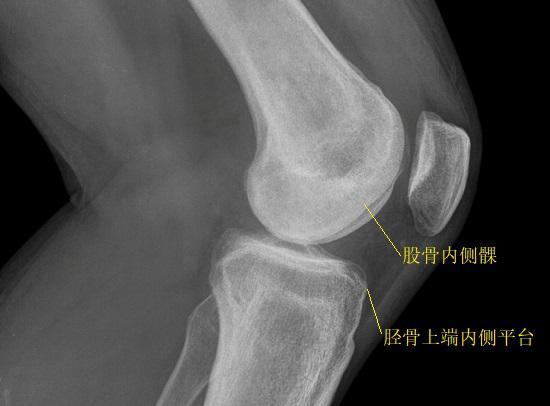

PCL损伤的分级 所谓后抽屉试验,其过程是这样的:患者仰卧且屈膝90度,双足平置于床并保持放松。检查者坐于床上以抵住患者双足使之固定,一手握患侧踝,另一手握小腿上端,并尝试从前向后拉动小腿上端,若小腿出现移动,则为后移阳性,表明可能存在后交叉韧带的松弛和断裂(包括部分断裂)。需要注意的是,在该试验之前,应确认是否存在前交叉韧带断裂或松弛的情况,若存在前交叉韧带断裂,应将胫骨受力后与股骨的相对位置(胫骨上端内侧平台与股骨内侧髁的相对位置)作为分级标准,而不是将胫骨上端向后移动的距离作为分级标准。在后抽屈试验中,胫骨向后移动的幅度在5mm以内,但胫骨上端内侧平台依然位于股骨内侧髁前方的,可视为PCL的I级损伤;胫骨向后移动的幅度在5mm-10mm之间,使胫骨上端内侧平台与股骨内侧髁处于同一额状面的,可视为PCL的II级损伤;胫骨向后移动的幅度大于10mm,使胫骨上端内侧平台处于股骨内侧髁之后的,则视为III级损伤。